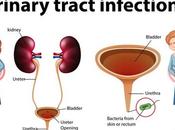

UTI (Urinary Tract Infection)

Urinary tract infection (UTI) is an infection in any part of your urinary system-such as kidneys, ureters, bladder and urethra. Most infections involve the lowe... Read more

Urinary Tract Infection

INTRODUCTION- Symptomatic presence of micro-organisms within the urinary tract i.e. your kidneys, ureters, bladder and urethra. Most infections involve the lowe... Read more